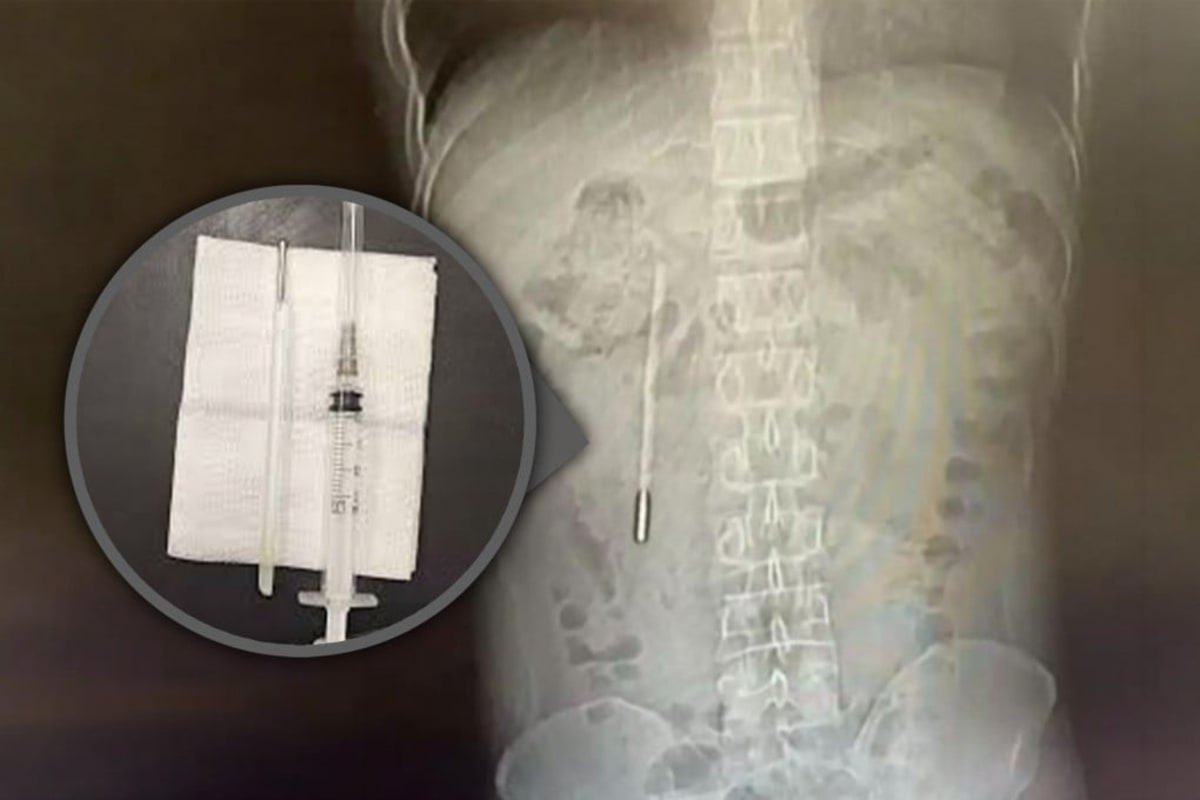

Doctors at The First Affiliated Hospital of Wenzhou Medical University ran an X-ray and spotted something unusual. A mercury thermometer was lodged in Wang's duodenum, its tip pressing dangerously against his intestinal wall.

Surgeons performed an emergency operation to remove the foreign object. The team successfully extracted the thermometer, which remained remarkably intact after spending 20 years inside Wang's body.

The only signs of its long journey were the faded temperature markings on the glass. Otherwise, the device looked much like it did the day a scared seventh-grader swallowed it.